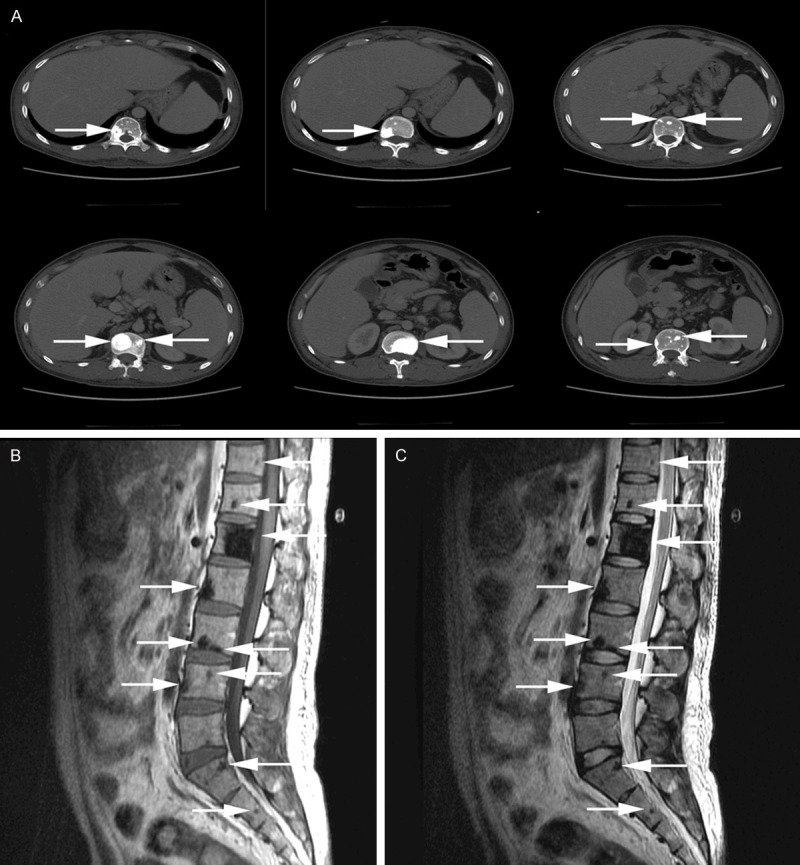

- Radiologists may miss sclerotic lesions unless specifically looking — CT with bone windows is far more sensitive than plain X-ray

- Can be sclerotic, lytic with sclerotic rim, or mixed ("soap bubble" appearance)

- Most common in axial skeleton — pelvis, spine, ribs, proximal extremities

- Most are less than 1 cm — CT with bone windows far more sensitive than plain X-ray

- ~50% have a single lesion; ~50% have multiple

- Sclerotic bone lesions

- CT (chest/abdomen/pelvis) with bone windows — NOT plain X-ray

- PET/CT if available

Clinical imaging: Shi XF et al., "Multimodal imaging and clinical characteristics of bone lesions in POEMS syndrome," Int J Clin Exp Med 2015;8(5):7467-76, PMC4509235. Chen YH et al., CCR3, PMC4831386. Case Reports in Medicine, PMC3195534. All images reproduced under Creative Commons licenses.